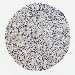

LIVER CANCER - Protein expressioni

A mouse-over function shows sample information and annotation data. Click on an image to view it in a full screen mode. Samples can be filtered based on level of antibody staining by selecting one or several of the following categories: high, medium, low and not detected. The assay and annotation is described here.

Antibody stainingi

Antibody staining in the annotated cell types in the current human tissue is reported as not detected, low, medium, or high, based on conventional immunohistochemistry profiling in selected tissues. This score is based on the combination of the staining intensity and fraction of stained cells.

Each image is clickable and will lead to virtual microscopy that enables deeper exploration of all samples and also displays staining intensity scores, fraction scores and subcellular localization as well as patient and tissue information for each sample.

Antibody HPA017998

Antibody HPA018864

Staining

High

Medium

Low

Not detected

Intensity

Strong

Moderate

Weak

Negative

Quantity

>75%

75%-25%

<25%

None

Location

Nuclear

Cytoplasmic/membranous

Cytoplasmic/membranous,nuclear

Cholangiocarcinoma

Carcinoma, Hepatocellular, NOS